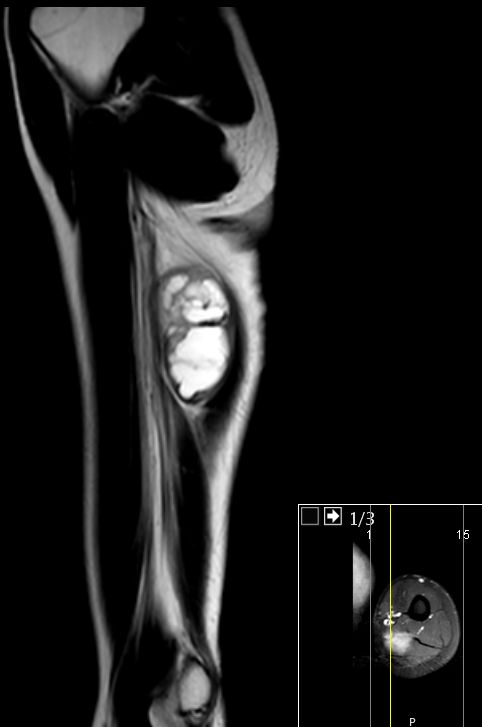

| Neurinom | 26-jährige Frau mit einem Tumor am linken Oberarm. Makroskopisch 45mm großes gekapseltes Gewebsstück mit rötlich-gelblichen weich-elastischen Schnittflächen. Mikroskopisch: Bekapselten spindelzelligen Tumor. Kein Nachweis von Kernatypien oder vermehrten Mitosen. Eingelagert sind ektatische, teilweise thrombosierte Blutgefäße mit Einblutungen und Blutungsresiduen in Form von Hämosiderophagen. Immunhistologisch positiv mit S100. CD34, Alpha Aktin, Caldesmon und CD 68 negatic. Die proliferative Aktivität ist nicht erhöht. Benigner, peripheren Nervenscheidentumor, Neurinom. ![]() |

![]() |